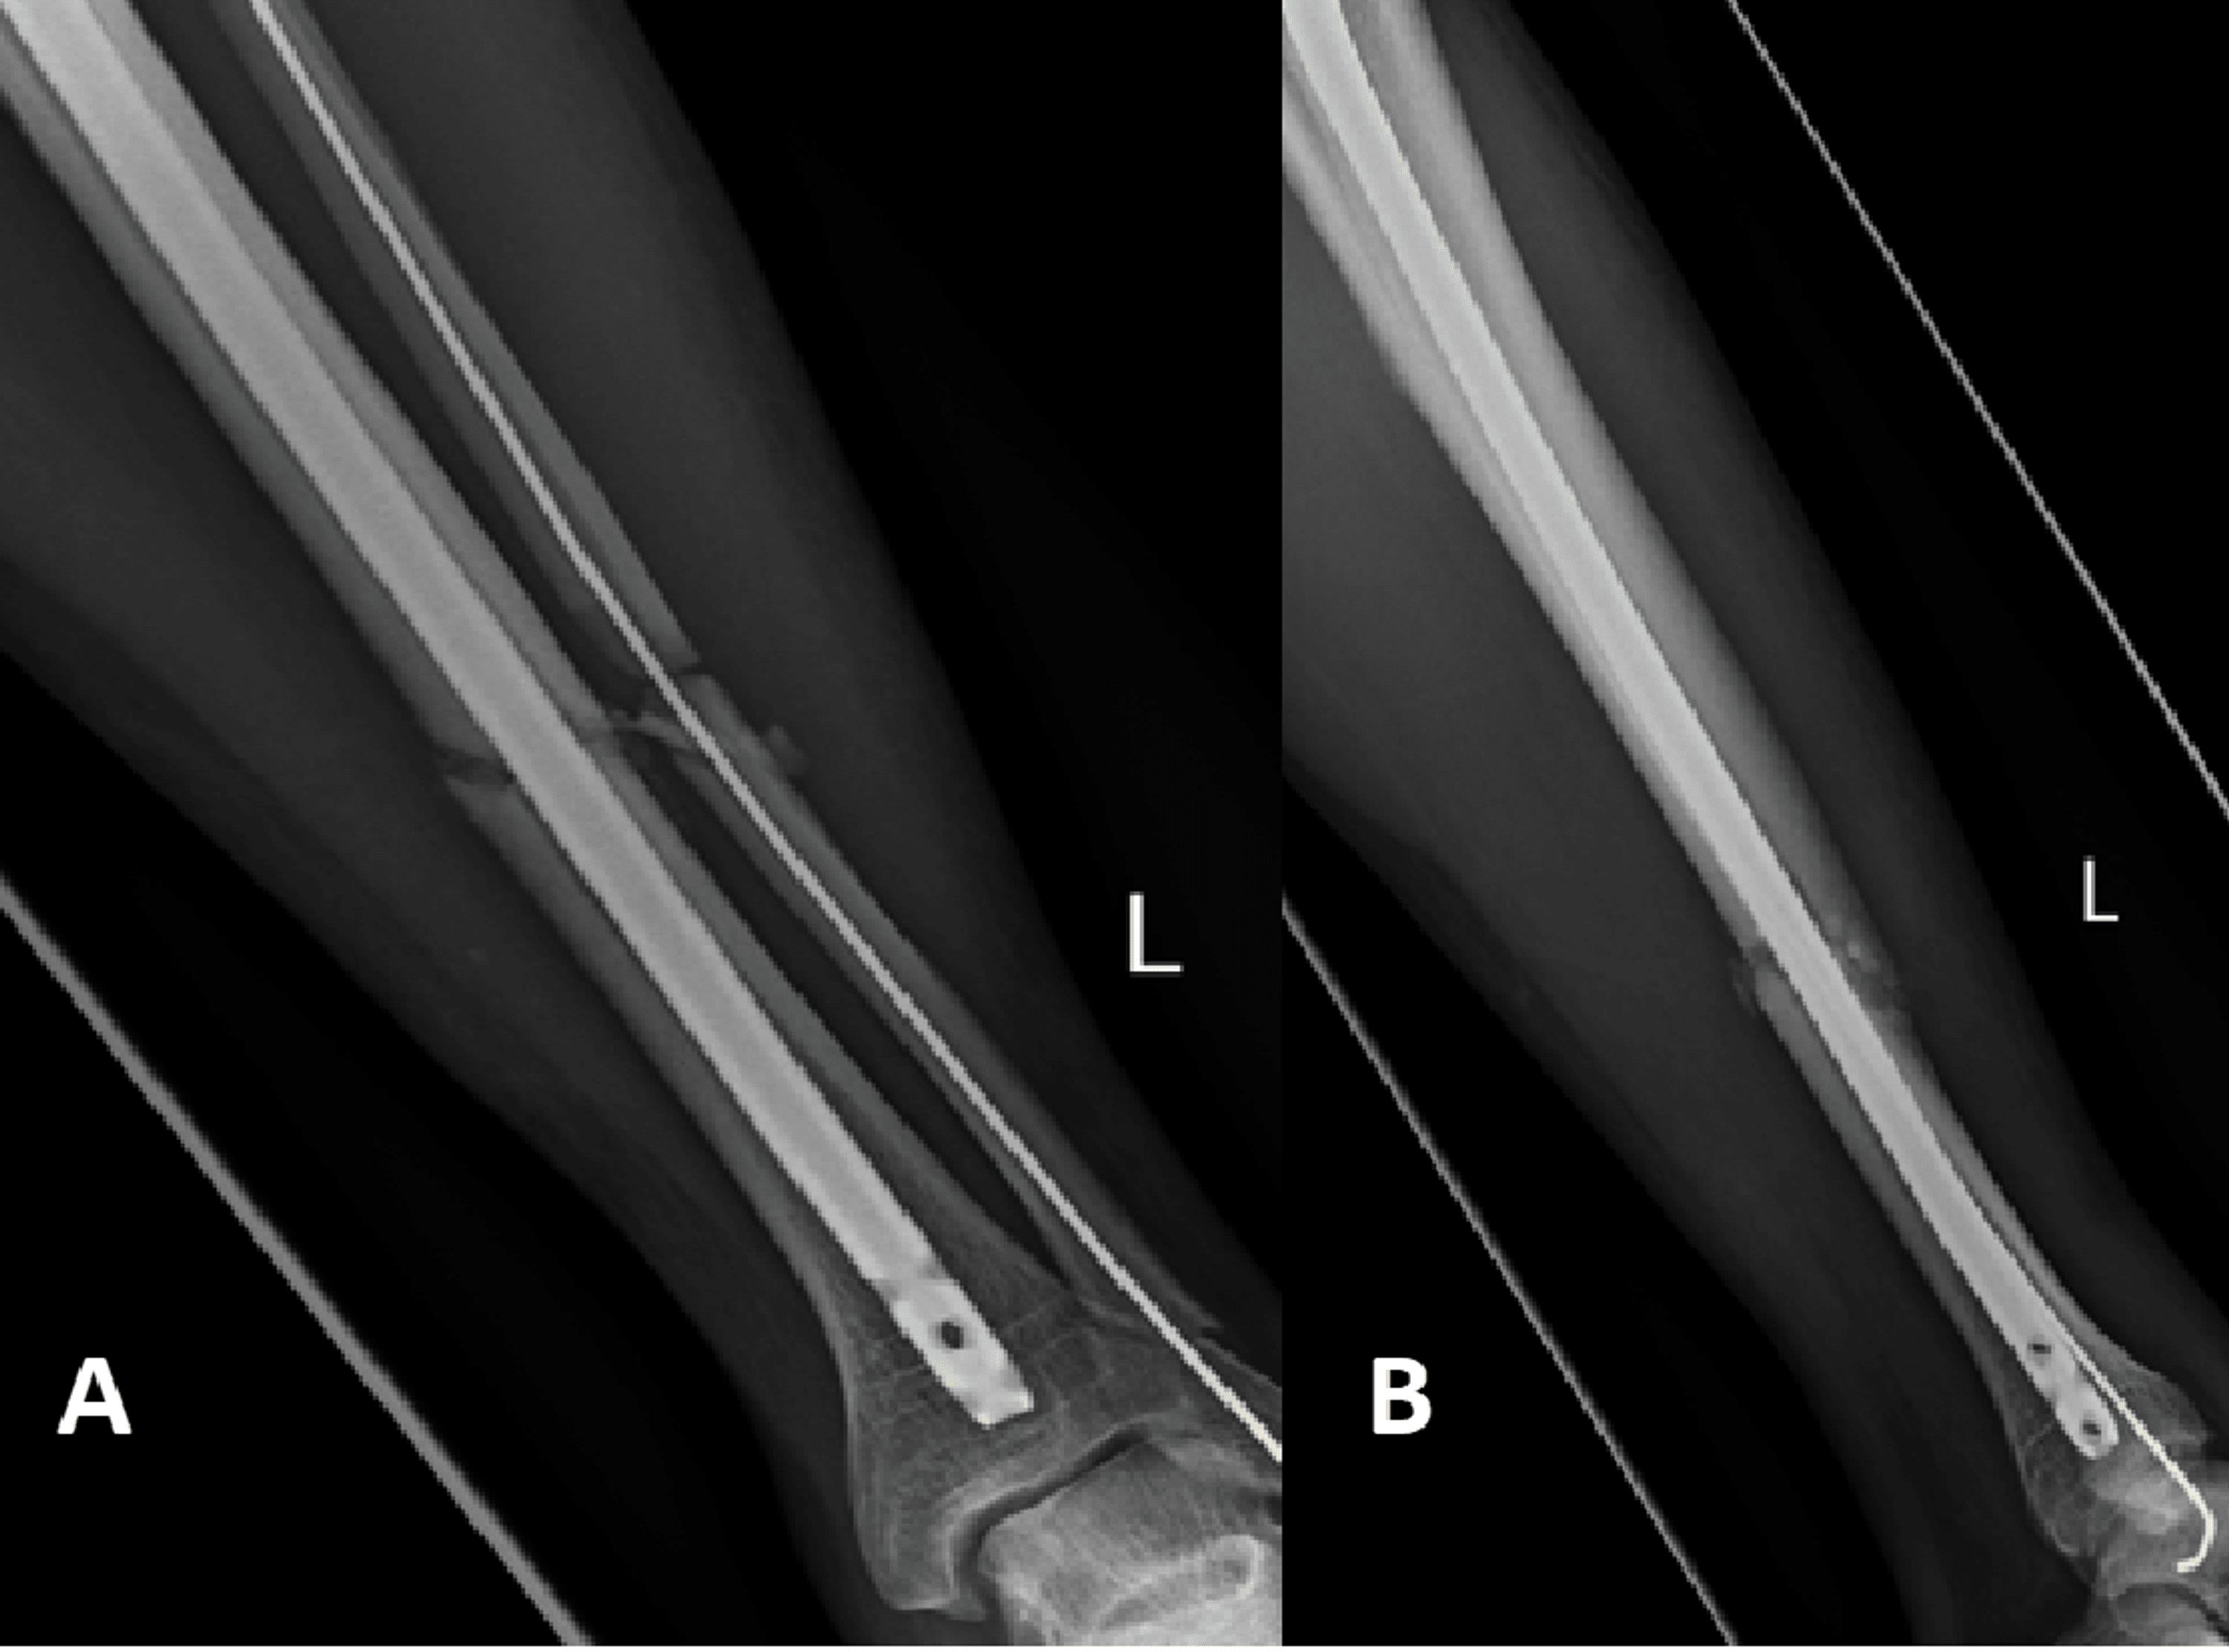

Radiological images of a nonunion of the distal tibia (A) with Non-Union Radiological Features Emerging evidence from the literature is discussed in this review with a focus on ct and ultrasound as useful imaging. Oligotrophic nonunion shows some of the radiographic and biologic features of each type and typically presents biologic potential. Although edema is evident in the adjacent marrow, there is no abnormal enhancement postgadolinium to suggest infection. Important to discern injury mechanisms,. Non-Union Radiological Features.